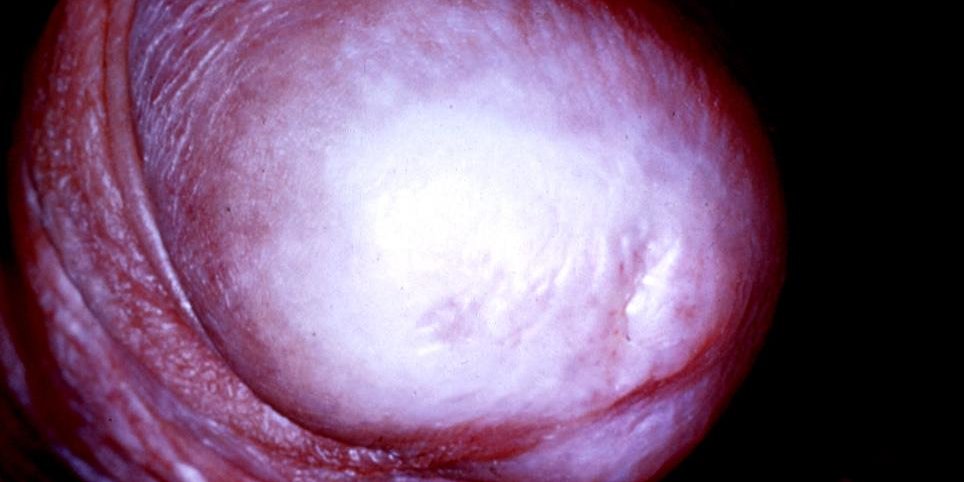

Balanitis kserotika obliterans (BKO) ya da penis yerleşimli liken sklerozis, nedeni tam olarak bilinmeyen, kronik ve ilerleyici seyir gösteren bir hastalıktır. BKO, edinsel yani sonradan gelişen mea stenozunun (üretra ağzının darlığı) en sık nedenleri arasında yer alır. BKO, erkeklerde ön üretra ve tüm üretra darlıkların %5-8’inden sorumludur. Hastalık en sık penis başı ve sünnet derisini tutmaktadır. Çocuklardaki fimozisin yaklaşık olarak %10’undan sorumludur. BKO nadiren de olsa kanser hastalığına dönüşebilir. BKO, erişkinlerde daha çok sünnet olmamış ve orta yaşlı erkeklerde görülür.

Hastalığın erken dönemlerinde herhangi bir belirti olmayabilir. İlerleyen dönemlerde penis başında renk değişikliği, idrar yaparken yanma, sızlama, penis başında duyarsızlık, kaşıntı, akıntı, cinsel ilişki sırasında penis ereksiyon halinde iken ağrı ve idrar akım hızında azalma gibi belirtiler görülebilir.